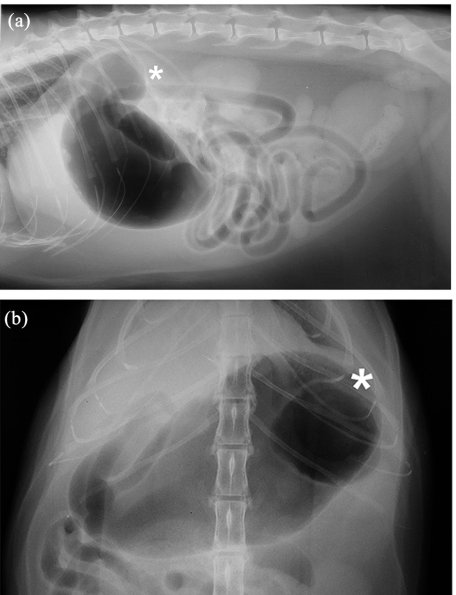

위게실의 경우 주증은 예상대로 구토, 식욕부진, 체중 감소가 주증으로 방사선 검사에서

이런 양상으로 GDV하고는 다른 양상의 공기주머니가 이중으로 있는 특징을 보인다.

당연하겠지만 이렇게 위내 gas가 충진되어 있지 않다면 진단하기 어려울 것이다.

때문에 필요에 따라 조영 검사를 해 볼 필요가 있지만 조영 검사에서도 위 연동운동의 상태에 따라 오인될 수도 있기 때문에 반복해서 여러번 촬영해야 진단될 수 있다.